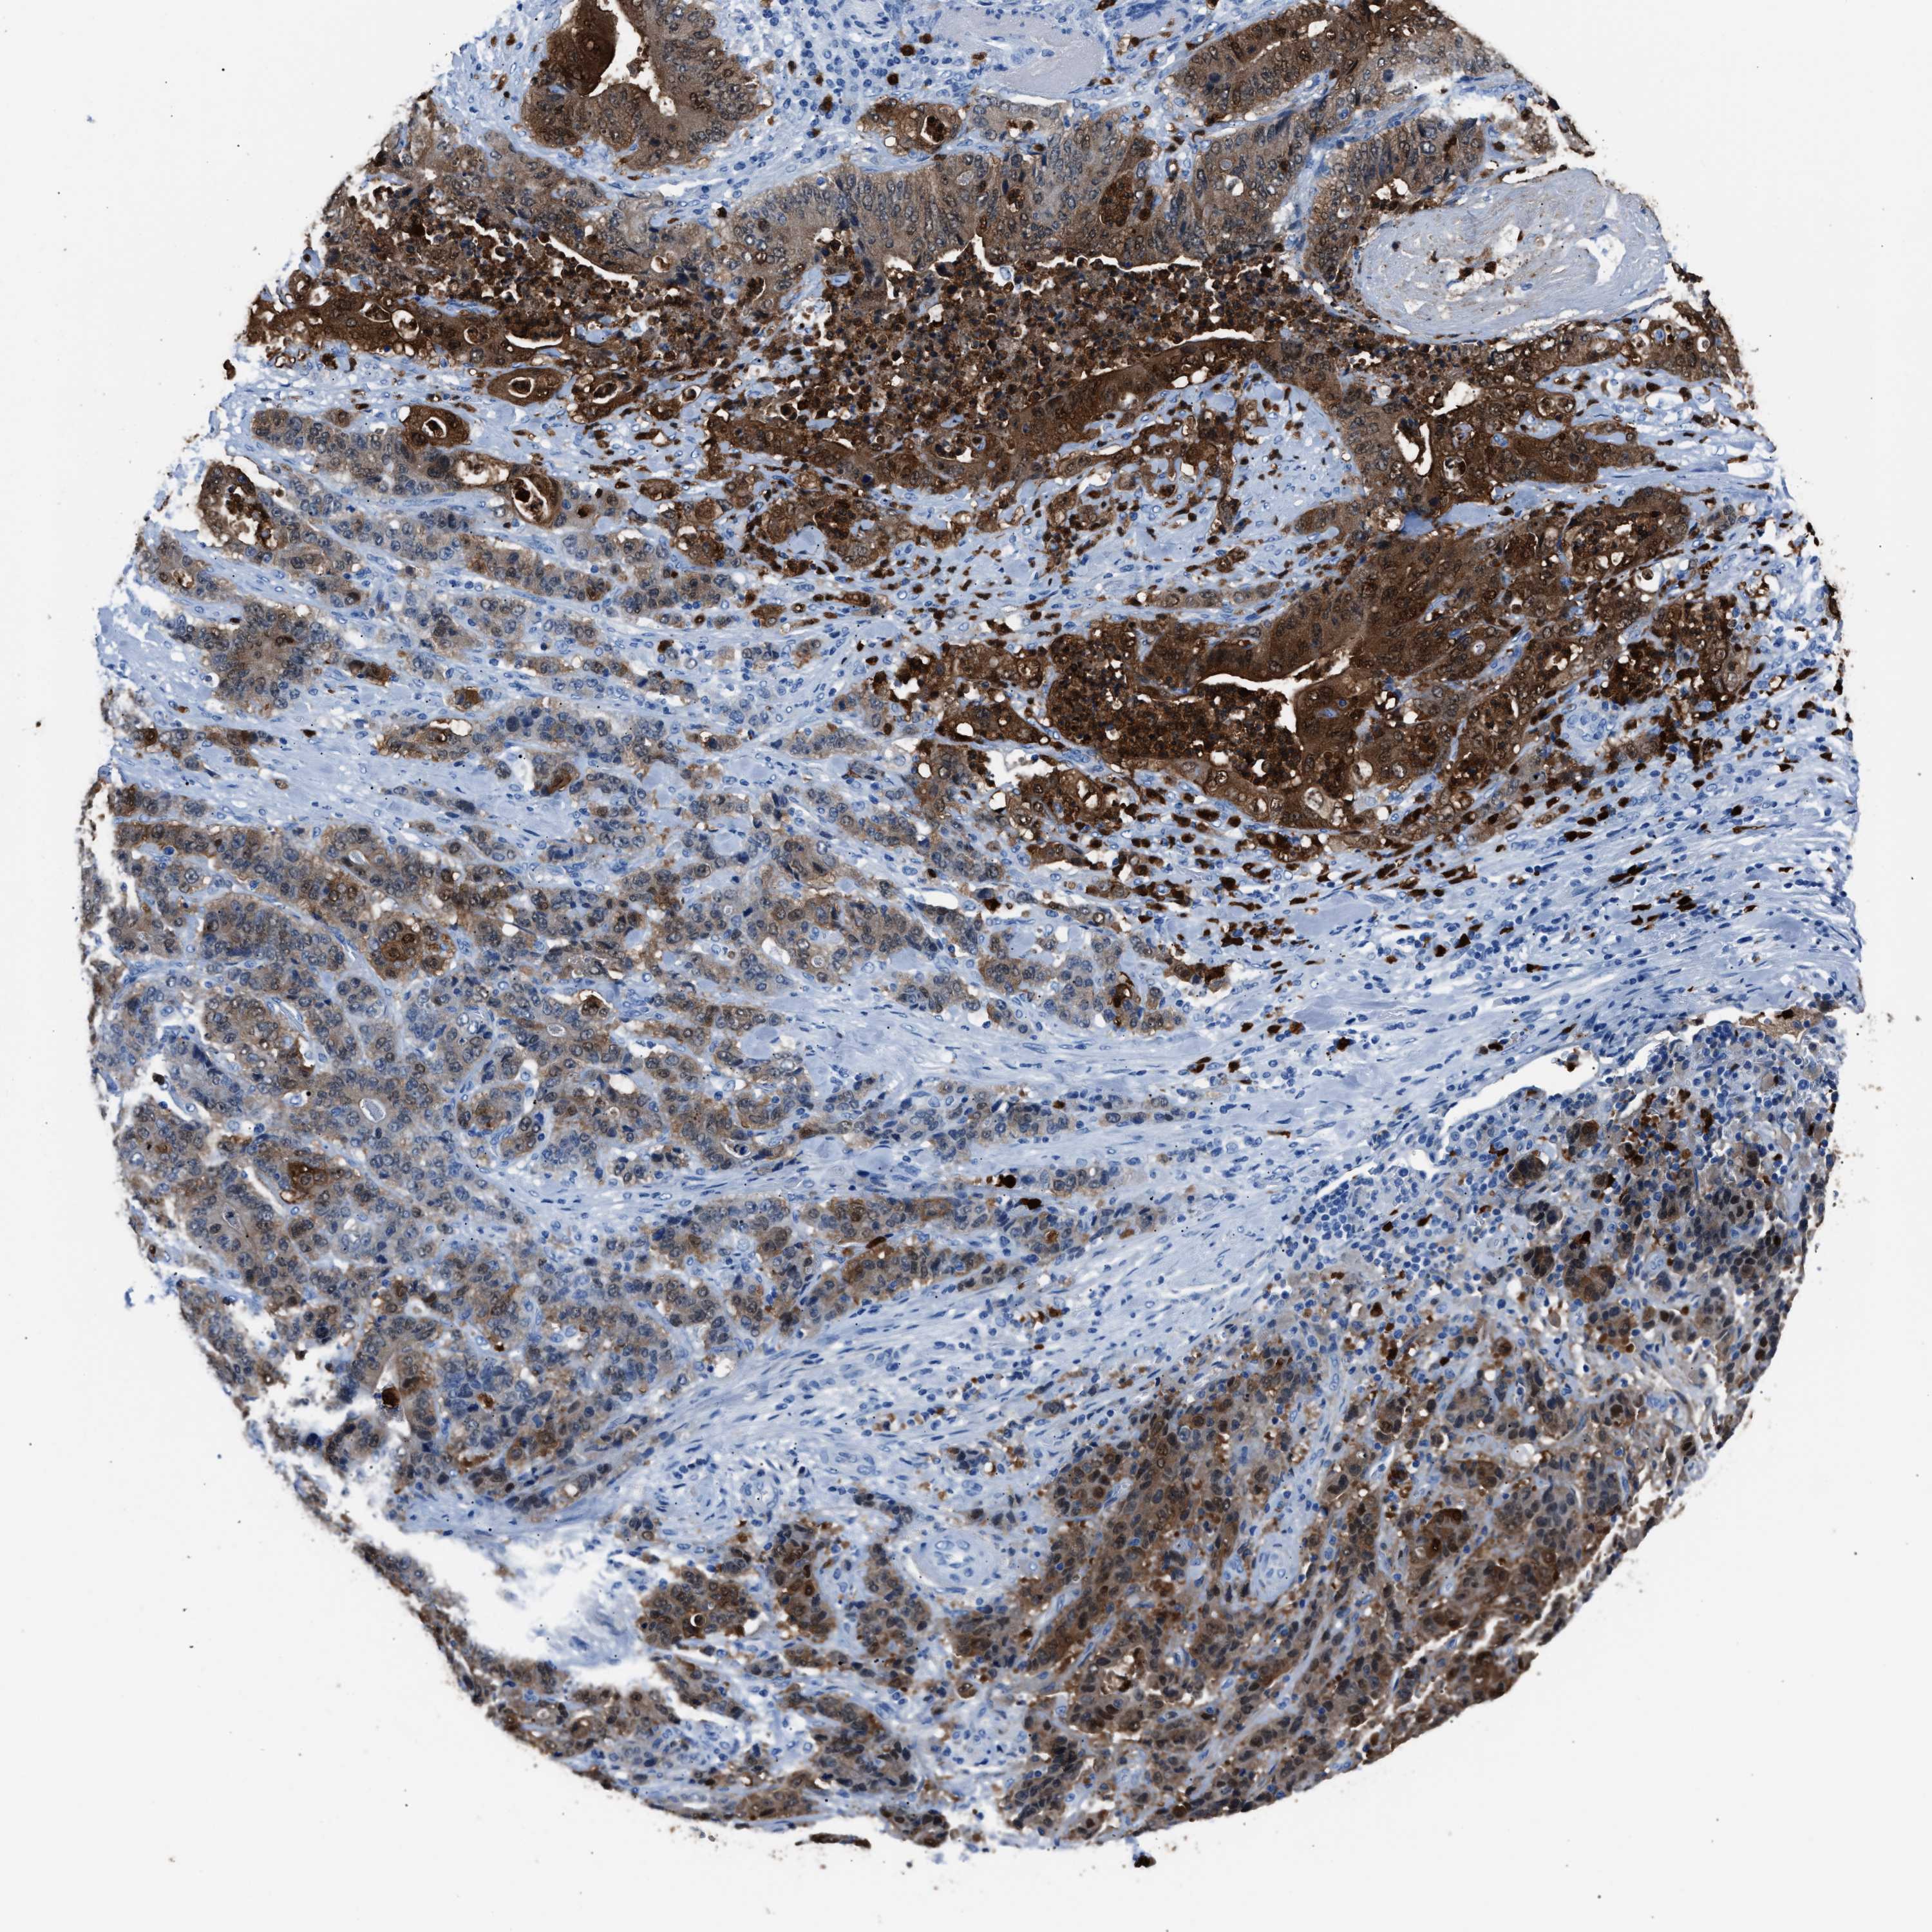

STOMACH CANCER - Protein expressioni

A mouse-over function shows sample information and annotation data. Click on an image to view it in a full screen mode. Samples can be filtered based on level of antibody staining by selecting one or several of the following categories: high, medium, low and not detected. The assay and annotation is described here.

Note that samples used for immunohistochemistry by the Human Protein Atlas do not correspond to samples in the TCGA dataset.

Antibody stainingi

Antibody staining in the annotated cell types in the current human tissue is reported as not detected, low, medium, or high, based on conventional immunohistochemistry profiling in selected tissues. This score is based on the combination of the staining intensity and fraction of stained cells.

Each image is clickable and will lead to virtual microscopy that enables deeper exploration of all samples and also displays staining intensity scores, fraction scores and subcellular localization as well as patient and tissue information for each sample.

Antibody HPA019502

Staining

High

Medium

Low

Not detected

Intensity

Strong

Moderate

Weak

Negative

Quantity

>75%

75%-25%

<25%

None

Location

Nuclear

Cytoplasmic/membranous

Cytoplasmic/membranous,nuclear

Adenocarcinoma, NOS